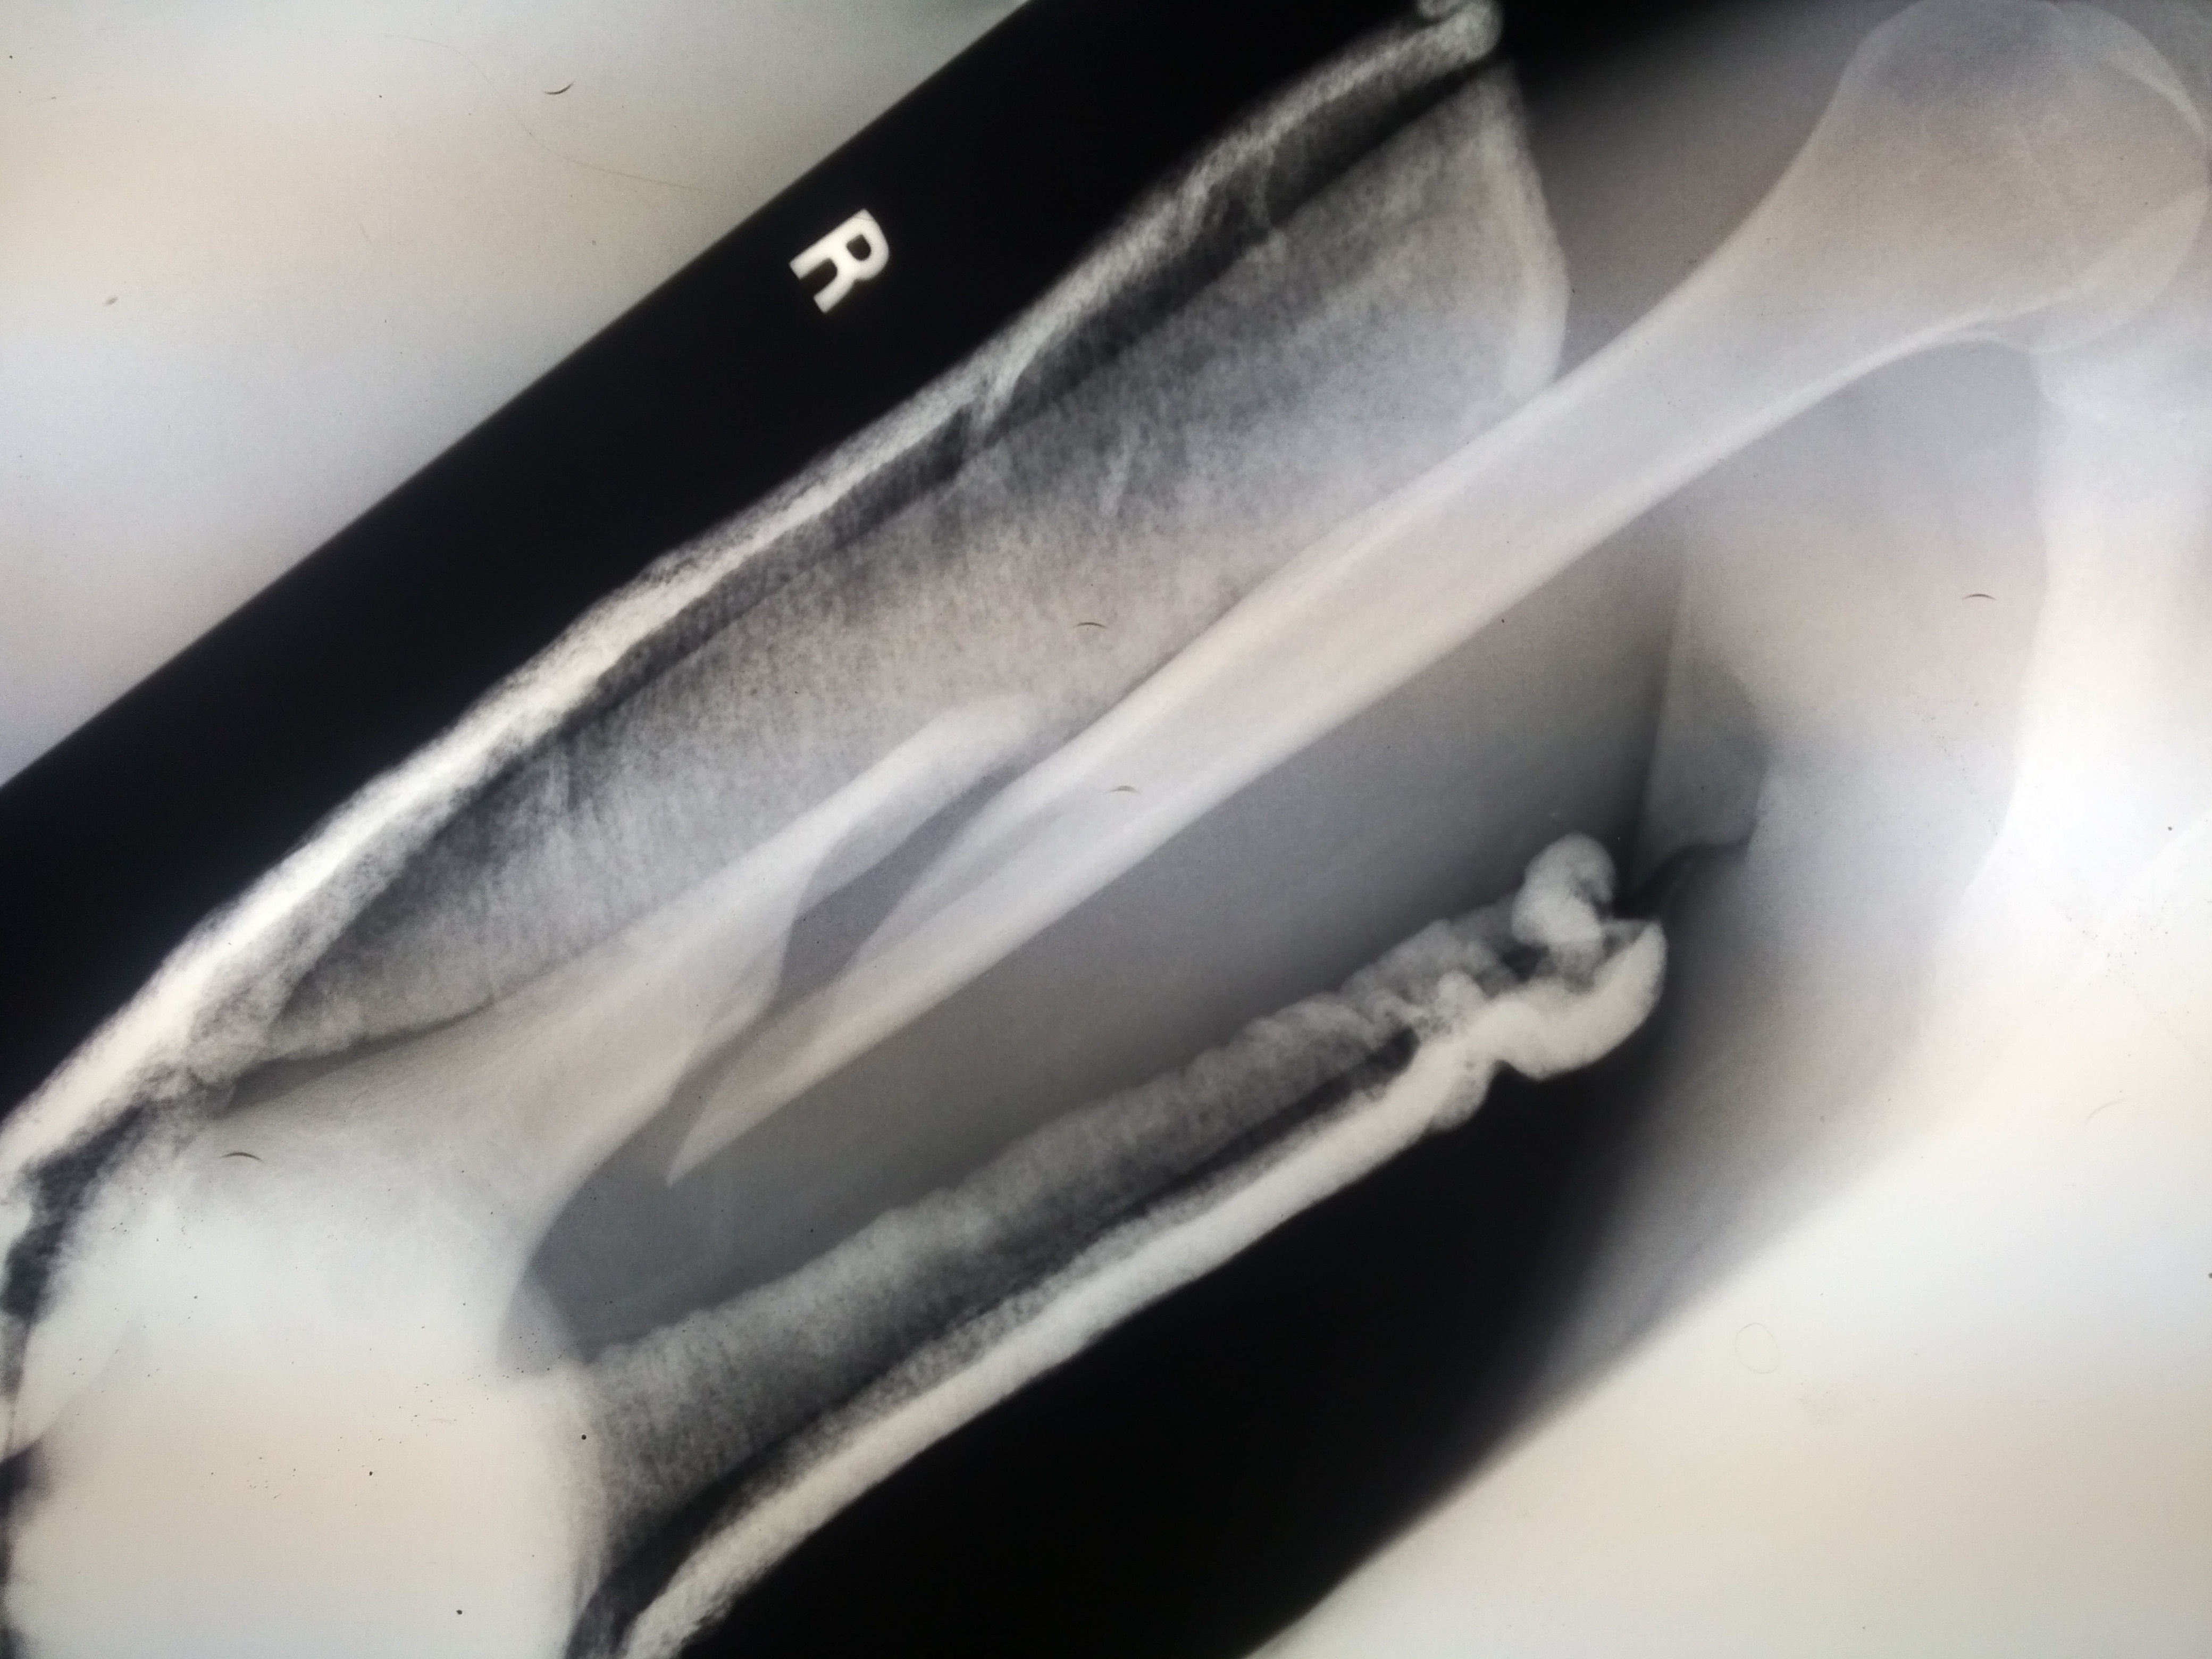

4. 진단

골절은 병력 청취 및 신체 검사를 통해 진단할 수 있다. 진단을 확인하기 위해 종종 방사선 영상 검사를 시행한다.[1] 특정 상황에서는 탈구 및 골절-탈구를 배제하기 위해 인접 관절의 방사선 검사가 필요하다.[1] 투사 방사선 촬영술만으로는 불충분한 경우, 컴퓨터 단층 촬영(CT) 또는 자기 공명 영상(MRI)이 필요할 수 있다.[1]